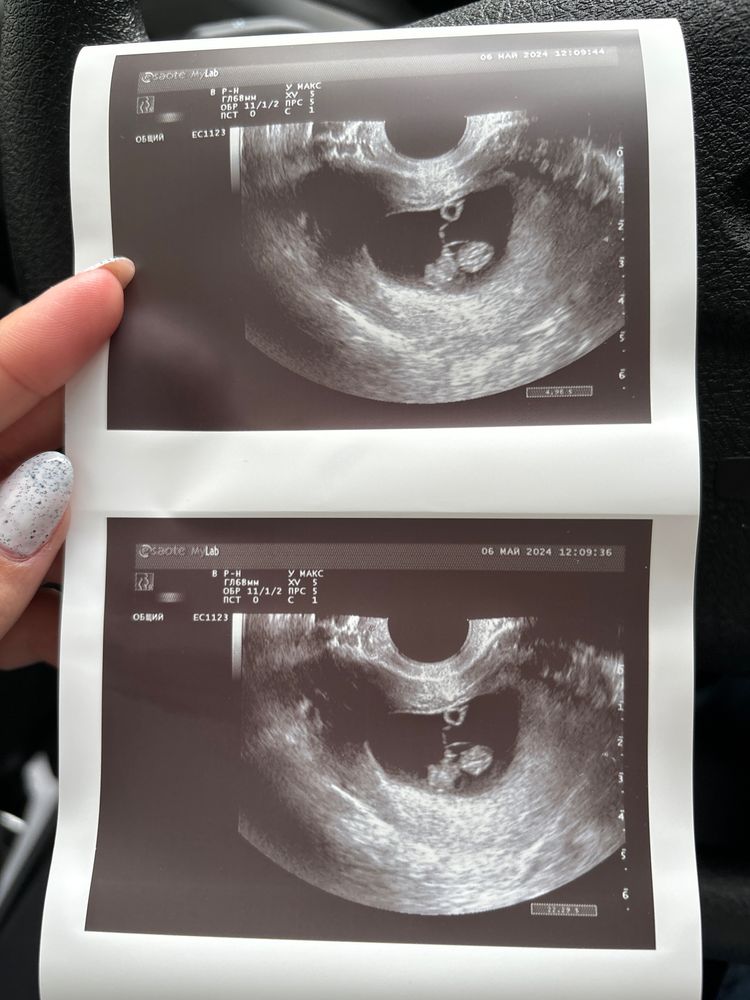

ИзображениеДевчат, подскажите тоже, узи вагинальное, 8 неделек

Похоже на девочку ,потом напишите ,интересно работает ли метод ,у меня совпал кстати